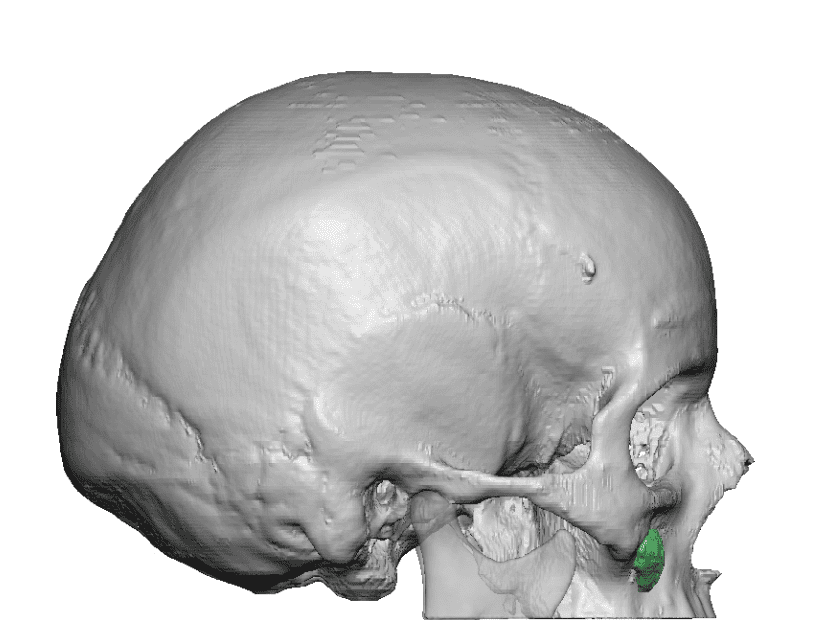

Desire for change of head shape from front view form an inverted V shape to a rounder and wider head shape.

Placement of custom extended forehead-temporal implants through incisions in the crease behind the ear. (he had a prior back of head skull implant which is green in the implant designs and which the head widening implants partially covered it)

Desire for change of head shape from front view form an inverted V shape to a rounder and wider head shape.

Placement of custom extended forehead-temporal implants through incisions in the crease behind the ear. (he had a prior back of head skull implant which is green in the implant designs and which the head widening implants partially covered it)